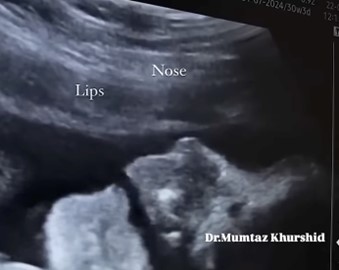

Η διαδικασία της κατάποσης είναι σημαντική για τη θρέψη και την ενυδάτωση του ανθρώπου και παίζει πρωταρχικό ρόλο στη διατήρηση τόσο της καλής μας υγείας όσο και της ποιότητας ζωής μας. Ο μηχανισμός της κατάποσης εμφανίζεται στην εμβρυϊκή ηλικία των τριών μηνών, επιτρέποντας στο έμβρυο να καταπίνει αντανακλαστικά το αμνιακό υγρό (βλ. παρακάτω εικόνες).